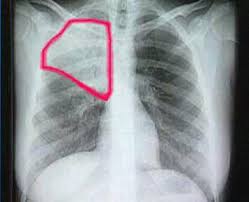

Pero lo más importante de esta semana que entra se producirá el martes. Sixto, mi suegro, tiene atorado un manguito y necesita que el médico se lo quite, así como un filtro que tiene estropeado. Yo rezo para que se quede en una simple reparación, de esas en las que sólo te cobran la mano de obra, y pronto esté dándose esos largos paseos por Málaga que tanto le gustan.